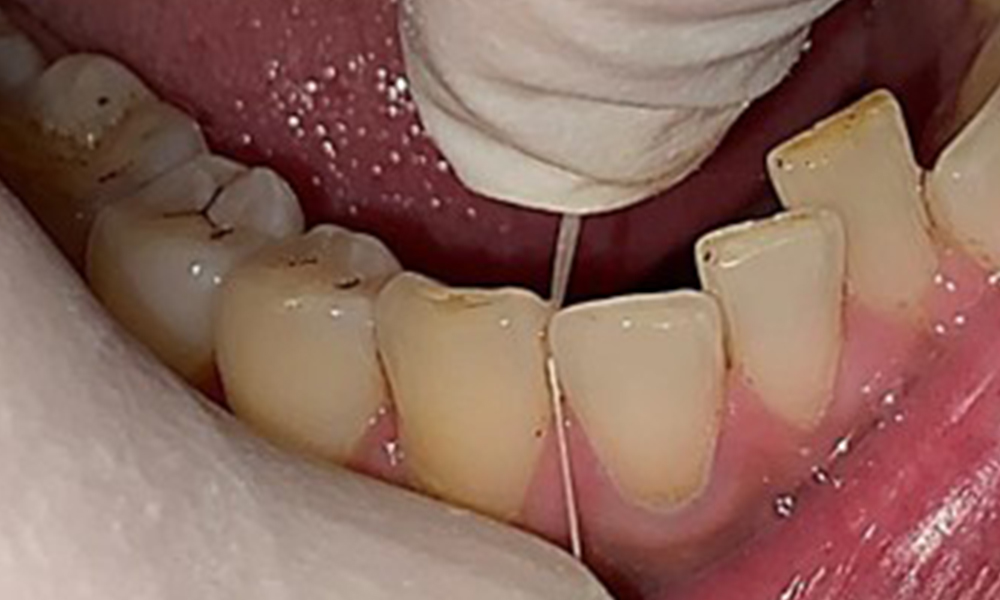

L'instruction et la motivation sont des éléments importants de ces rendez-vous. Il est important que les patients comprennent et adoptent un bon comportement en matière d'hygiène intrabuccale à domicile. L'accumulation de plaque est particulièrement évidente dans les régions cervicales (Fig. 8).

Les flèches indiquent les accumulations de plaques dans la région cervicale.

Fig. 8: Les flèches indiquent les accumulations de plaques dans la région cervicale., © Dr R. Krapf

Il convient d'en discuter avec le patient et d'améliorer la technique de brossage des dents. Il est recommandé d'utiliser une brosse à dents souple pour l'hygiène intrabuccale à domicile en raison de la présence d'érosions et d'attritions.

Il est également nécessaire de vérifier que les brosses interdentaires - utilisées quotidiennement par ce patient - sont de la bonne taille et encouragent une utilisation cohérente (Fig. 9). Une bonne hygiène intrabuccale minimise le risque de parodontite lié au tabagisme.

Utilisation des brosses interdentaires dans la zone proche de 44/45

Fig. 9: Utilisation des brosses interdentaires dans la zone proche de 44/45, © Dr R. Krapf